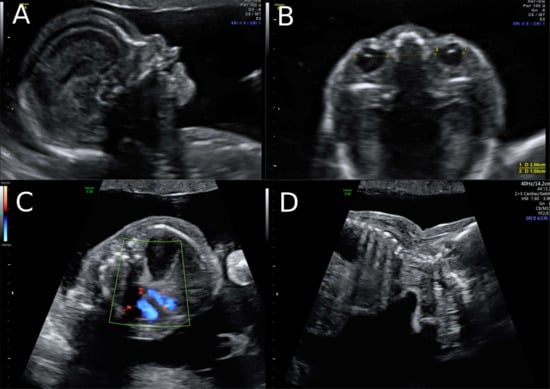

A 38-year-old women with a dichorionic-diamniotic twin pregnancy, after in-vitro fertilisation, attended routine first trimester screening at 13 + 4 weeks of gestation. One of the twins (fetus I) pair showed normal NT measurement and a low risk for chromosomal abnormalities, whereas the other twin (fetus II) presented an increased NT of 5.2 mm, the position of the fetal heart in the middle of the thorax, and hyperechogenic kidneys (Figure 1). At this stage, the patient declined invasive diagnosis. At 15 + 5 weeks of gestation, additional findings to the ones above, including hydronephrosis, skin oedema, and a right-sided clubfoot, have been observed. Subsequently, amniocentesis in the affected fetus was performed and revealed a 46, XY karyotype. Estimated fetal weight for both were average for the gestational age but abdominal circumference (AC) of the second twin was at the 95th percentile. At 22 + 0 weeks of gestation, the overall estimated fetal weight of fetus II was above the 95th percentile and a nuchal fold of 8.1 mm with general oedema of the skin was present. The ultrasound scan additionally showed a striking profile (Figure 2). All measurements (HC-AC-FL) were above the 95th percentile. A suspicion of left-sided diaphragmatic hernia as well as hyperechogenic kidneys, increased in size and polycystic appearance, and a hypoplasia of genitalia have been identified. Furthermore, the scan revealed a polyhydramnios (DIP 10 cm). Due to the polyhydramnios of fetus II, fetus I has been compromised in a similar process as twin-to-twin transfusion syndrome, although fetal development and amniotic fluid have been normal (Figure 3).

Figure 1. Ultrasound findings in the 1st Trimester. (A) Increased Nuchal Translucency (NT) at 13 + 5 weeks of gestation in twin II. (B) A simple cystic structure in the abdomen, most probably a gastrointestinal duplication cyst. (C) Hyperechogenic kidneys. (D) Malposition of the fetal heart in the chest at 13 + 5 weeks. The position of the fetal heart in the middle of the thorax.